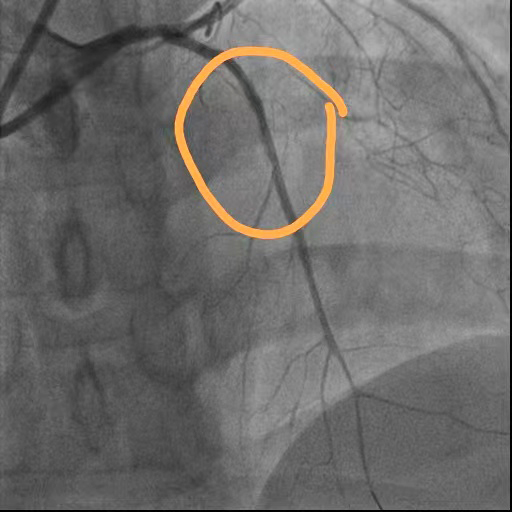

术前

回旋支狭窄

前降支近段闭塞

右冠脉狭窄